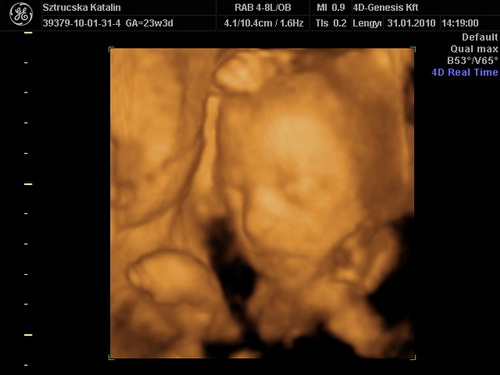

Tök jó, hogy ilyen szép nagyok a csajok! Holnap mindenképp megtippeltetem magunkat is Apánkkal. Már nekem is fúrja az oldalam a kíváncsiság. A mi fejünk sem volt túl nagy a múltkor...de már a 4D-n is úgy volt, hogy az oldalsó átmérő kisebb volt, elölről hátra nagyobb (tehát oldalról kicsit lapított a búránk) de így a körméret meg pont megfelelő lett. Pedig a képen milyen kis holdvilág képe van Nimókának.